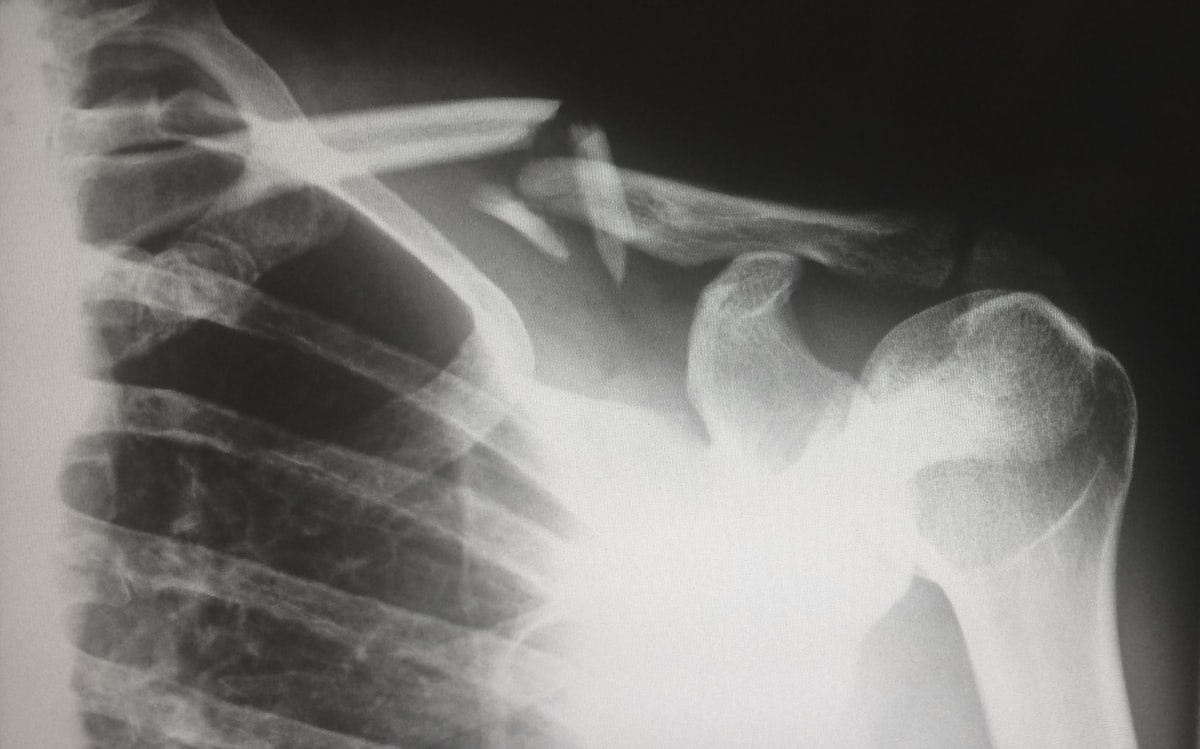

Рентгенологическое исследование органов грудной клетки, костей и суставов

Рентгенография костей, суставов и позвоночника (в различных проекциях), рентгенография черепа, придаточных пазух носа и зубов. Выполняются специальные укладки черепа (по Шюллеру, по Майеру).